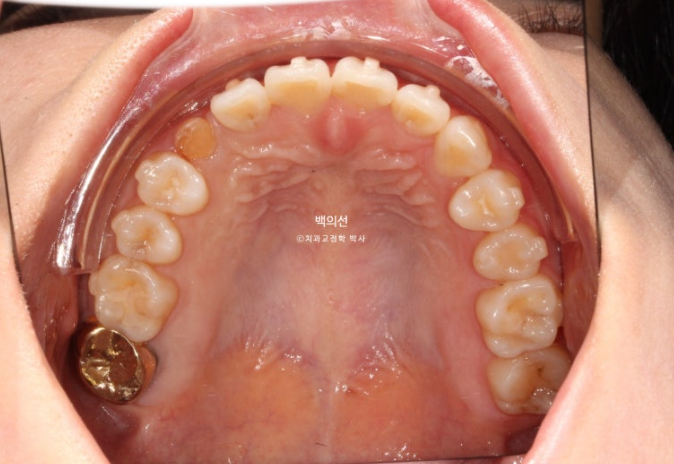

잔존유치는 영구치 송곳니가 매복되는 바람에 남아있는 상태입니다.

잔존유치의 뿌리가 썩 튼튼하지는 않으나, 동요도는 전혀 없어 쓸때까지 쓰기로 합니다.

그런데 잔존유치에 교정력을 가할경우, 안그래도 약한 유치 뿌리가 녹을 수 있어서 잔존유치는 치료기간 내내 치아이동 없이 위치 잠금으로 계획해야 하고 어태치먼트조차 붙이지 않는 게 좋습니다.

색이 어두운 치아는 잔존유치에 레진을 덮어놓은 상태이고 이번기회에 재교정을 하면서 이 치아도 변색된 레진을 제거하고 라미네이트든 크라운이든 깔끔하게 치료를 원하셨습니다.

오래 전 했던 교정으로 어금니 교합은 나쁘지 않은 상태입니다.

인비절라인 라이트로 앞니 배열과 뿌리를 뼛속으로 깊이 넣어주는 치료를 권유드렸습니다.

또한 블랙트라이앵글 사이즈를 줄이기 위한 치간삭제도 계획하기로 했습니다.